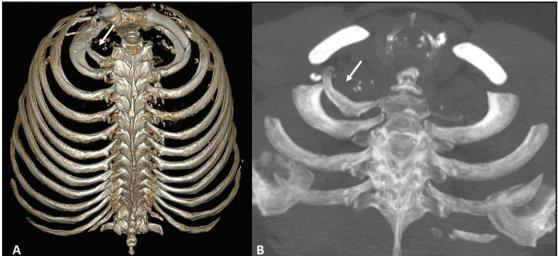

Observe as imagens, abaixo, e indique a anomalia da caixa torácica demonstrada:

Fonte: https://www.scielo.br/j/rb/a/cV8MMVtMjmJKSKMDNHKpR4G/?format=pdf&lang=pt

O arco costal bífido de von Luschka, é caracterizado por uma duplicidade na sua porção anterior, nos seus aspectos ósseos e/ou cartilaginosos, geralmente acometendo o: